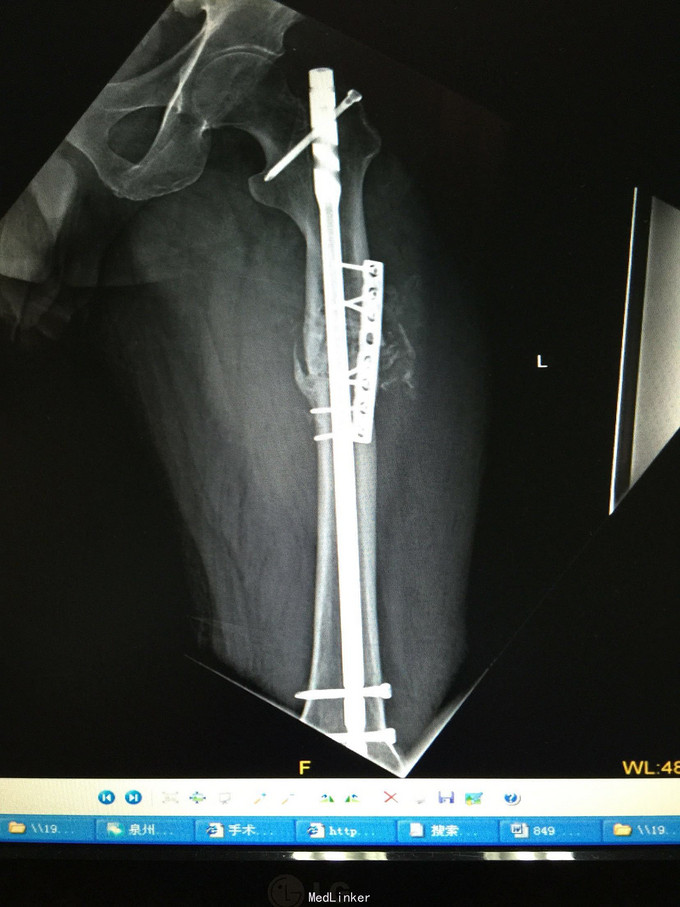

左股骨中上段骨折术后骨不连

诊断:左股骨中上段骨折术后骨不连 处理:左股骨骨折术后骨不连断端清理+防旋钢板内固定+取髂骨植骨术

术后半年 讨论 考虑股骨中上段骨折 应力集中 近段一枚螺钉稳定性不够?